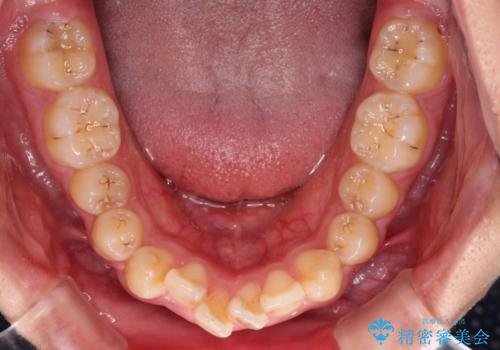

下顎の歯列は、奥歯が前方に傾斜し、前歯が上顎の歯の付け根に食い込むように内側に傾斜していました。

インビザラインで難儀する部分をワイヤー装置にて確実に改善しておくことで、インビザラインのみで行うよりも治療期間を短縮するとともに、より理想的な歯列に近づけて仕上げることができました。